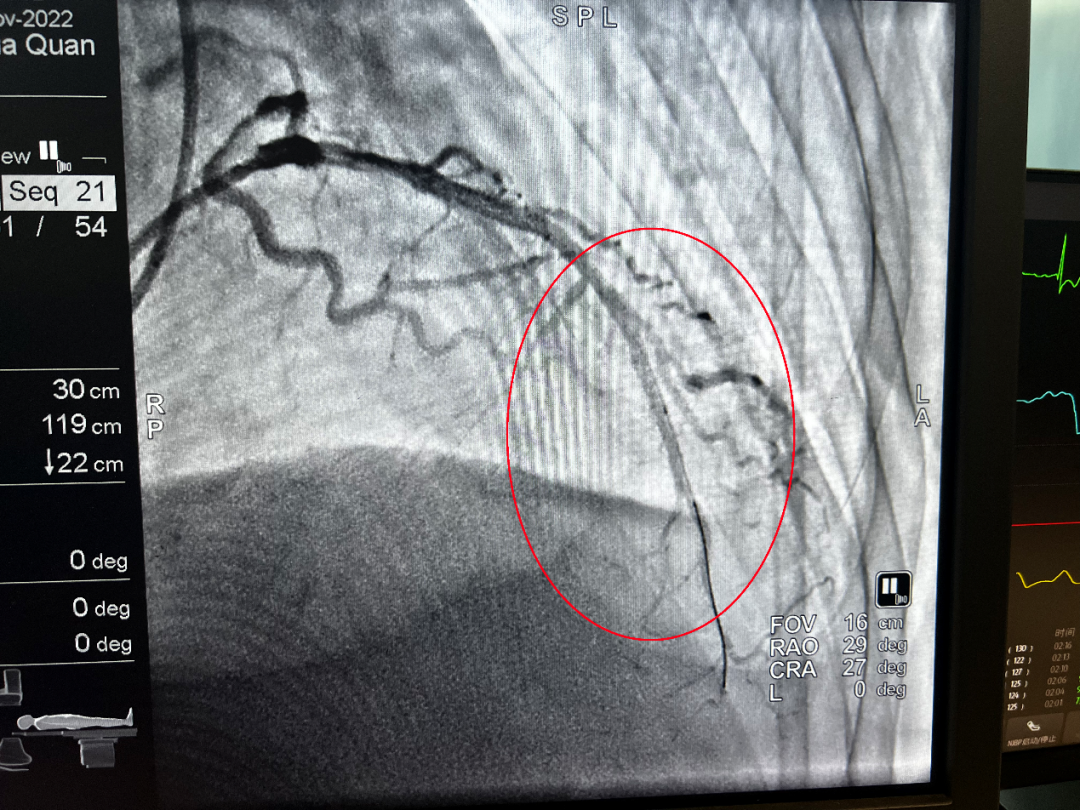

(介入后)

凌晨1點34分,導管室激活;1點38分,患者平車送入導管室;1點48分,穿刺成功;2點01分,導絲通過血管閉塞處……從王大爺首次醫療接觸到導絲通過,僅用時54分鐘。所有醫護人員繃緊神經,爭分奪秒,為患者開辟了一條脫離危險的綠色通道。術后,患者胸痛癥狀明顯緩解,轉危為安。